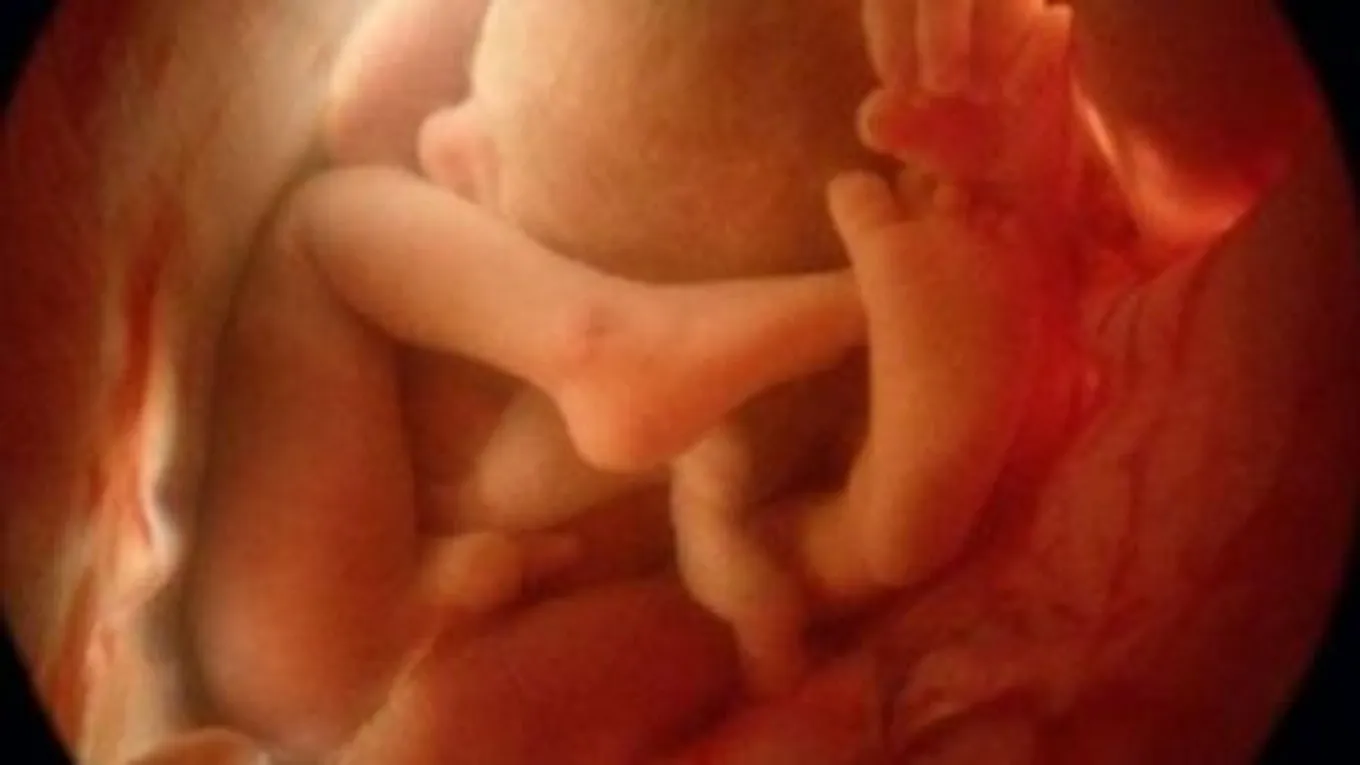

تبدأ الحركةُ الطبيعية الأولى للجنين في الفترة ما بين الأسبوعيْن السابع ومنتصف الأسبوع الثامن، ولكنها في هذه الفترة تكون غير ملموسة بالنسبة للأم، وتكون عبارة عن حركة فجائية تمتدّ لمدة لا تزيد عن ثانيتيْن، بحيث تظهر كحركة انتقاليّة لجسم الجنين ككل، علماً بأنّ طول الجنين هنا يبلغ حوالي اثنين سنتيمتر، وتكون نبضات قلبه سابقة لحركته، ويمكن مراقبتها في الأسبوع السادس من الحمل.

ومع مرور الأيّام تصبح حركة الجنين أكثر تعقيداً، وتبدأ أعضاؤه بأخذ وتحديد الوظائف الخاصة بها بشكلٍ تدريجي، وهذا بالتالي يؤثر على الحركة، بحيث تصبح متتالية ويفضل بينها مجموعة من الثواني فقط، وتستمر في التطوّر حتى يتمكن من فرد جميع أطرافه، وبالتالي تحريك جسده بأكمله، أمّا الوضوح في الحركة فيكون في الفترة ما بين الأسبوع الثامن عشر والثاني عشر، وتكون تارةً قوية وتارةً أخرى ضعيفة.